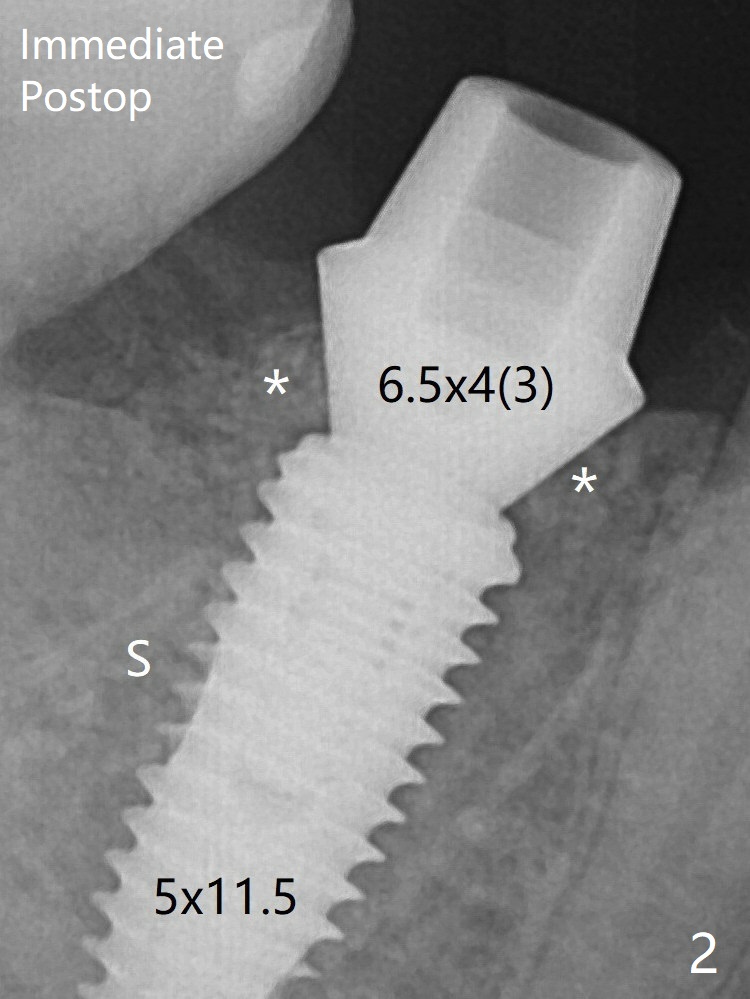

After extraction of #30 (Fig.1 (S: septum)), a 5x11.5 mm implant is placed with guide mainly in the mesial socket (mesial to the septum (S) with >35 Ncm; after immediate placement of a 6.5x4(3) mm abutment, allograft is placed (Fig.2 *). There is not too much loss of bone graft 4 months postop (Fig.5). In fact the mesial and distal sockets heal. The implant plateau is covered with the bone 8 months post cementation (Fig.6 arrowheads ( *: addition of porcelain for the distal gingival embrasure)).